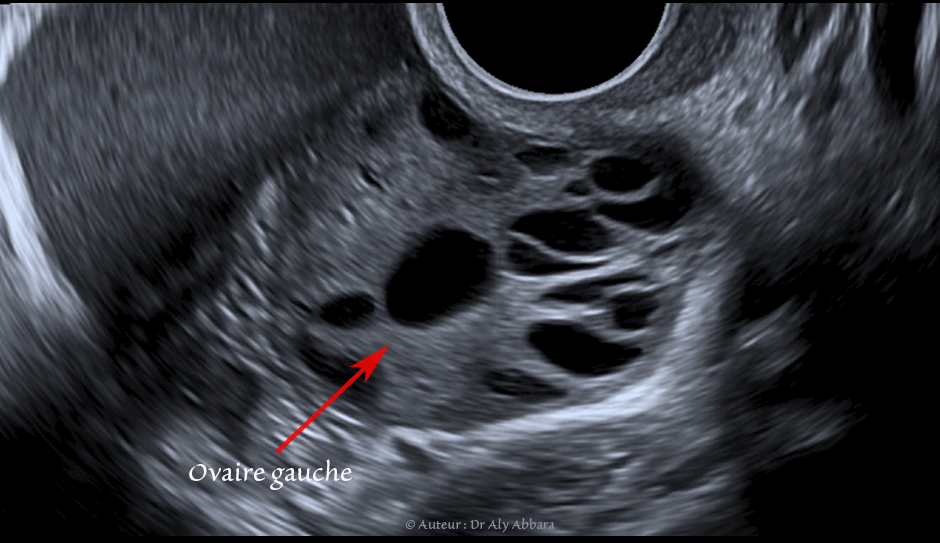

Image clinique échographique du petit pelvis et de l'ovaire gauche montrant le reflux rétrograde, tubo-abdominal de sang menstrul (sang des règles)

Image clinique cœlioscopique animée, puis images échographiques par voie endovaginale (une coupe sagittale médiane sur un utérus rétroversé et une coupe longitudinale sur l'ovaire gauche) ; ces images illustrent le reflux rétrograde, tubo-abdominal de sang menstruel qui peuvent survenir au cours de certaines règles (menstruation ou menstrues rétrogrades).

Chez cette patiente, ce reflux menstruel tubo-abdominal assez important était à l'origine de règles extrêmement douloureuses (dysménorrhéique). Les douleurs pelviennes sont provoquées par l'irritation et la réaction inflammatoire du péritoine pelvien par le contact avec le sang de la menstruation qui a atteint la cavité péritonéale par voie rétrograde (cavité utérine > lumière de la trompe gauche > cavité péritonéale).